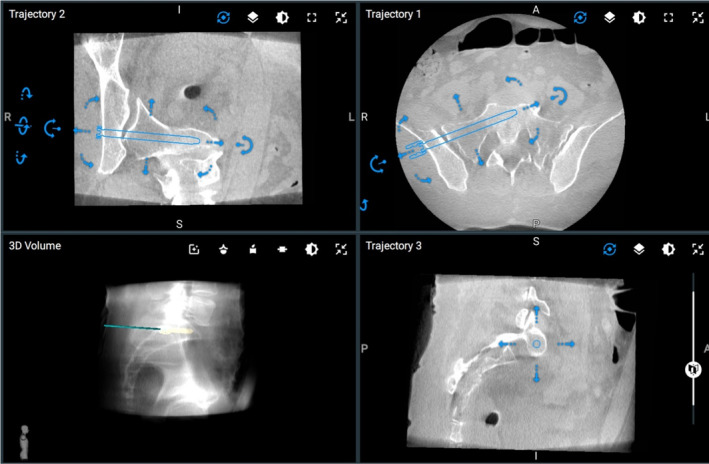

FIGURE 4.

Robotic plan for the SI screw.

The robot was draped in sterile fashion and brought near the surgical field. The surgical arm was brought into position in line with the planned screw trajectory. Robotic instruments were used to incise the skin. Blunt dissection was carried to bone. The robotic burr was used to open the outer cortex of the ilium. A 5.5 mm robotic tap was then placed to the limits of its depth. The tap was removed, and a robotic awl was placed against the bone. The central trocar from the awl was removed, and a 0.9 mm nitinol wire was placed through the awl into the path created by the tap. The wire position was maintained, and the awl as well as the end‐effector from the robot were removed. Using the nitinol wire as a feeler probe bone could be felt circumferentially through the entire course of the tapped bone. The robot was moved away from the surgical field. C‐arm was brought in, and the position of the wire in the bone was confirmed to be as planned. A 6.5 mm partially threaded screw was then placed over the wire under fluoroscopic control, and the wire withdrawn. Post‐procedure CT scan demonstrated placement of the screw exactly as planned (Figure 5).